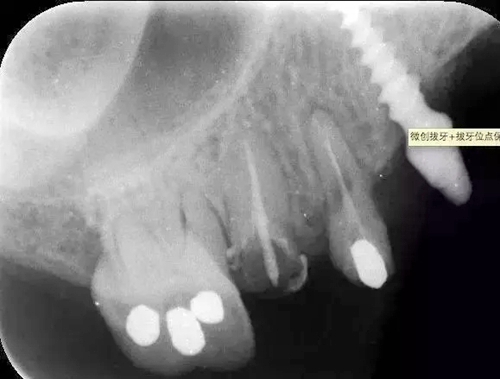

病例:患者,女、44歲,主訴:上頜烤瓷修復體脫落,要求重新烤瓷修復。

檢查:14根面旁穿,無法保留,15根長不足。

處理:14、15微創(chuàng)拔牙+拔牙位點保存術(shù)。

?術(shù)前的x線根尖片